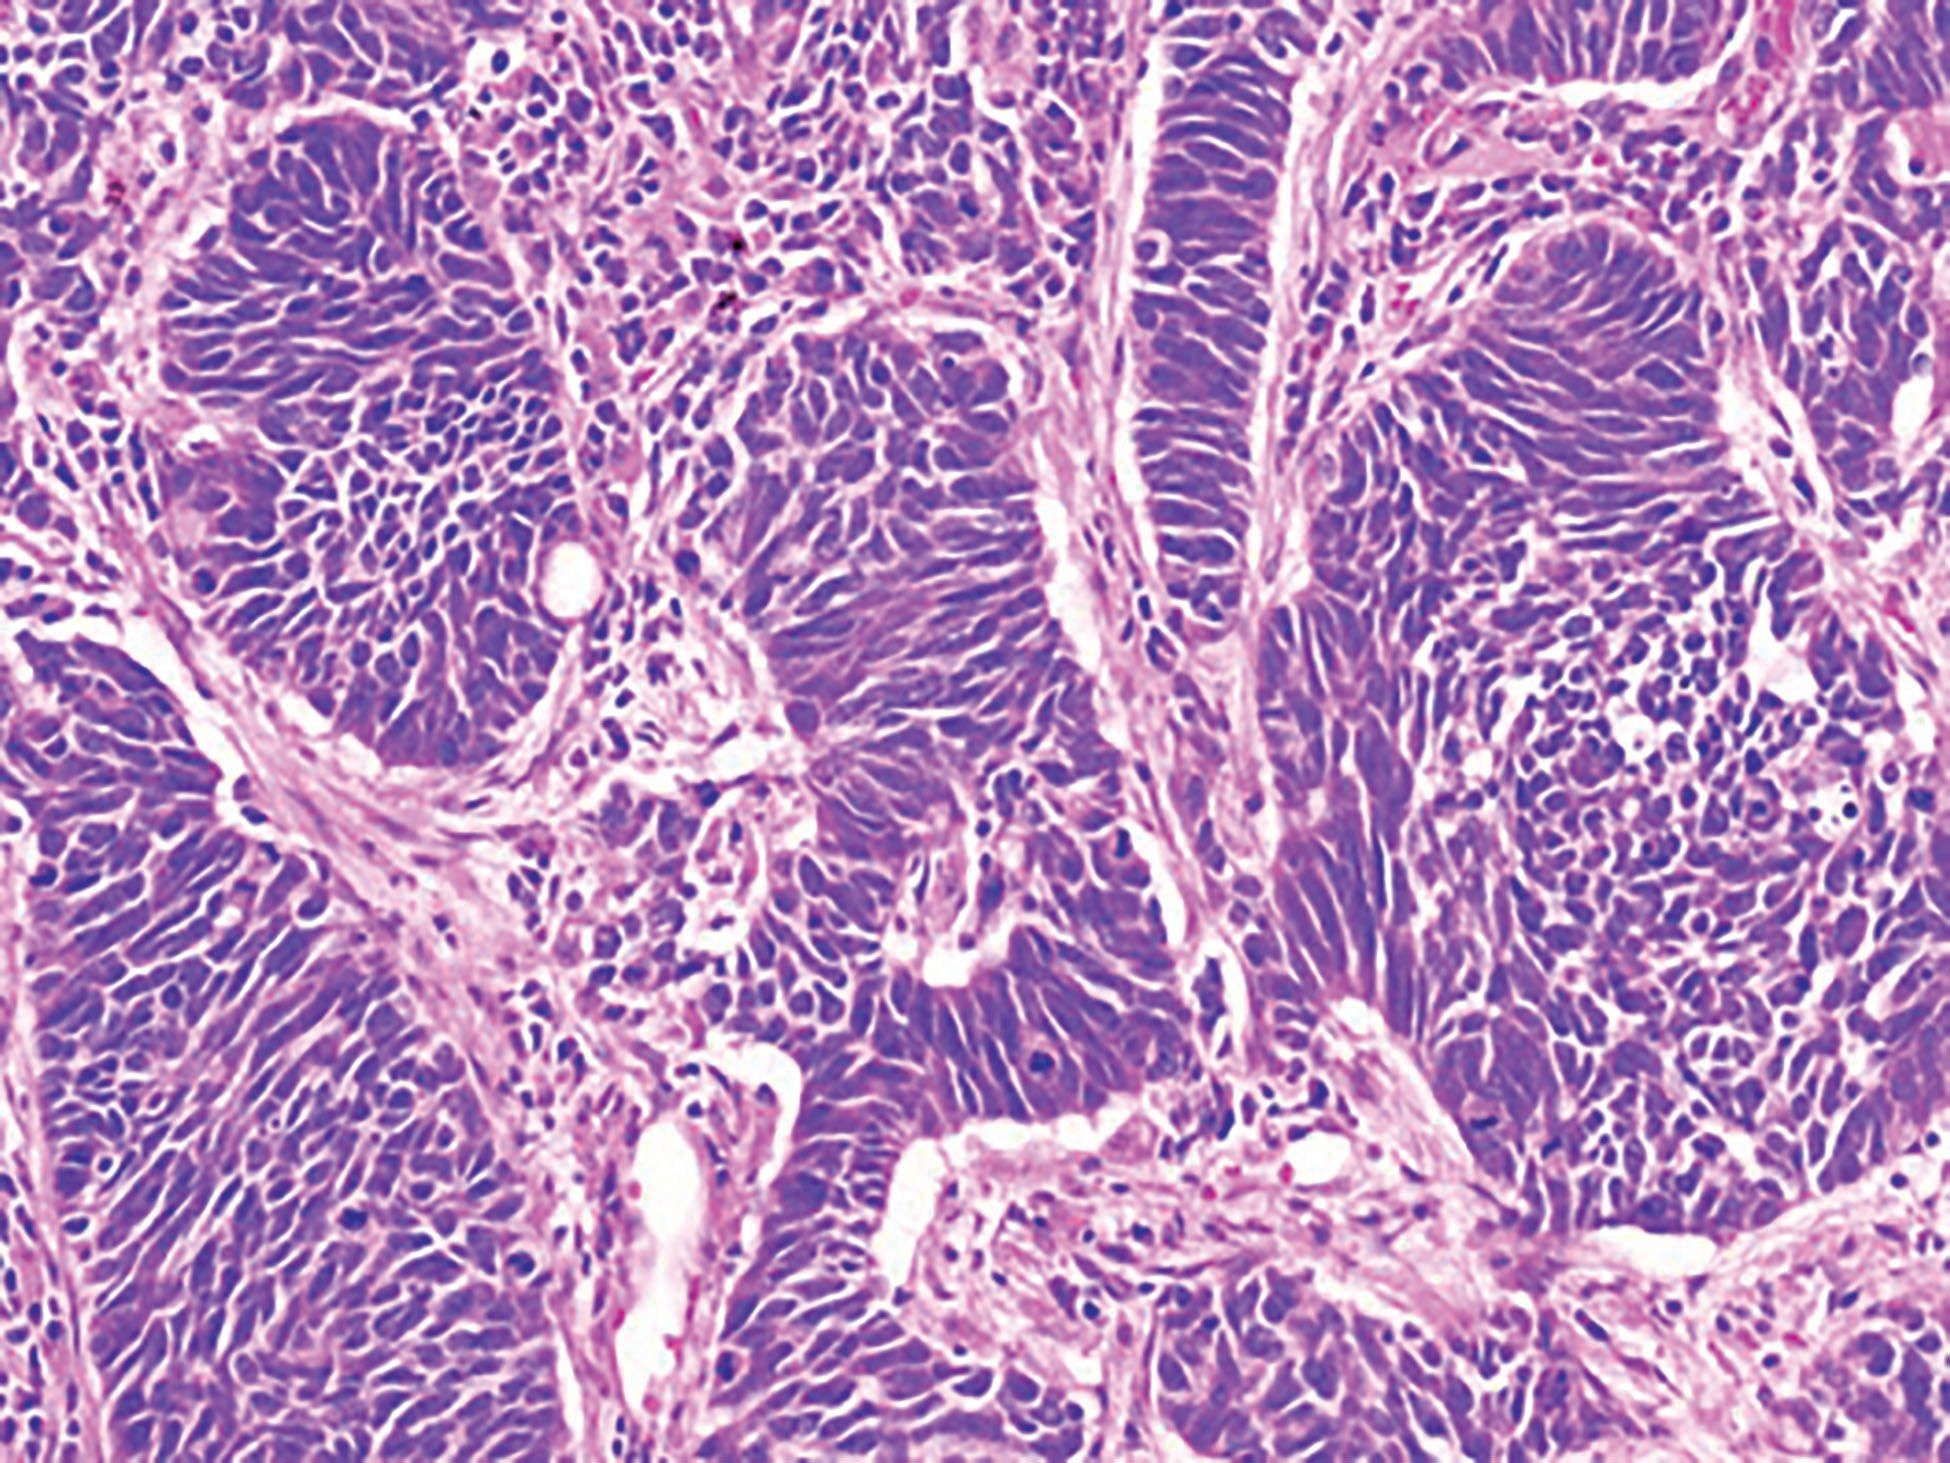

Figure 4A: Right upper lobe wedge resection: adenocarcinoma, lepidic pattern predominant (H&E, 200X magnification)

Figure 4B: Left upper lobectomy: small cell neuroendocrine carcinoma (H&E, 200X magnification)

A 70-year-old white woman with a 40 pack-year history of smoking has been on follow-up for previously detected abnormal lung nodules during the past 3 years. The most recent computed tomography (CT) scan revealed an increase in the size of the left upper lobe nodule-from 4 mm a year ago to 2 cm on the current CT scan. A CT-guided needle biopsy of this nodule revealed small cell lung carcinoma (Figures 1A and 1B). Further work-up with a positron emission tomography (PET) scan confirmed the left upper lobe lesion with a standard uptake value (SUV) of 12.7, and also revealed a right upper lobe nodule (1.1 cm in size) with an SUV of 2.1 (Figures 2A and 2B). Following multidisciplinary evaluation at the thoracic oncology tumor conference, the patient underwent initial bronchoscopy with ultrasound (endobronchial ultrasound [EBUS]) and biopsy of lymph node levels 10, 7, and 4, followed by a right-sided video-assisted thoracoscopic surgery (VATS) and a wedge resection of the right upper lobe nodule, and a left upper lobe lobectomy (Figure 3). Mediastinal lymph node dissection revealed no lymph node involvement. Pathology of the right upper lobe wedge resection revealed a 1.3-cm non–small cell lung adenocarcinoma, and pathology of the left upper lobe lobectomy revealed a 2.5-cm small cell lung carcinoma (Figures 4A and 4B). Both tumors had visceral pleural involvement and were resected with clear margins. The right upper lobe tumor was staged as pT2N0 and the left upper lobe tumor was staged as pT2N0 (per the 8th edition of the American Joint Committee on Cancer staging system).

Our patient had bilateral discordant histology at presentation making the diagnosis of SMPLC relatively straightforward. The right upper lobe nodule was an adenocarcinoma with a predominant lepidic pattern and involvement of visceral pleura and the left upper lobe tumor was a small cell carcinoma with lymphovascular invasion and visceral pleura involvement.